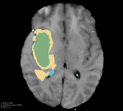

Deep neural network models used for medical image segmentation are large because they are trained with high-resolution three-dimensional (3D) images. Graphics processing units (GPUs) are widely used to accelerate the trainings. However, the memory on a GPU is not large enough to train the models. A popular approach to tackling this problem is patch-based method, which divides a large image into small patches and trains the models with these small patches. However, this method would degrade the segmentation quality if a target object spans multiple patches. In this paper, we propose a novel approach for 3D medical image segmentation that utilizes the data-swapping, which swaps out intermediate data from GPU memory to CPU memory to enlarge the effective GPU memory size, for training high-resolution 3D medical images without patching. We carefully tuned parameters in the data-swapping method to obtain the best training performance for 3D U-Net, a widely used deep neural network model for medical image segmentation. We applied our tuning to train 3D U-Net with full-size images of 192 x 192 x 192 voxels in brain tumor dataset. As a result, communication overhead, which is the most important issue, was reduced by 17.1%. Compared with the patch-based method for patches of 128 x 128 x 128 voxels, our training for full-size images achieved improvement on the mean Dice score by 4.48% and 5.32 % for detecting whole tumor sub-region and tumor core sub-region, respectively. The total training time was reduced from 164 hours to 47 hours, resulting in 3.53 times of acceleration.